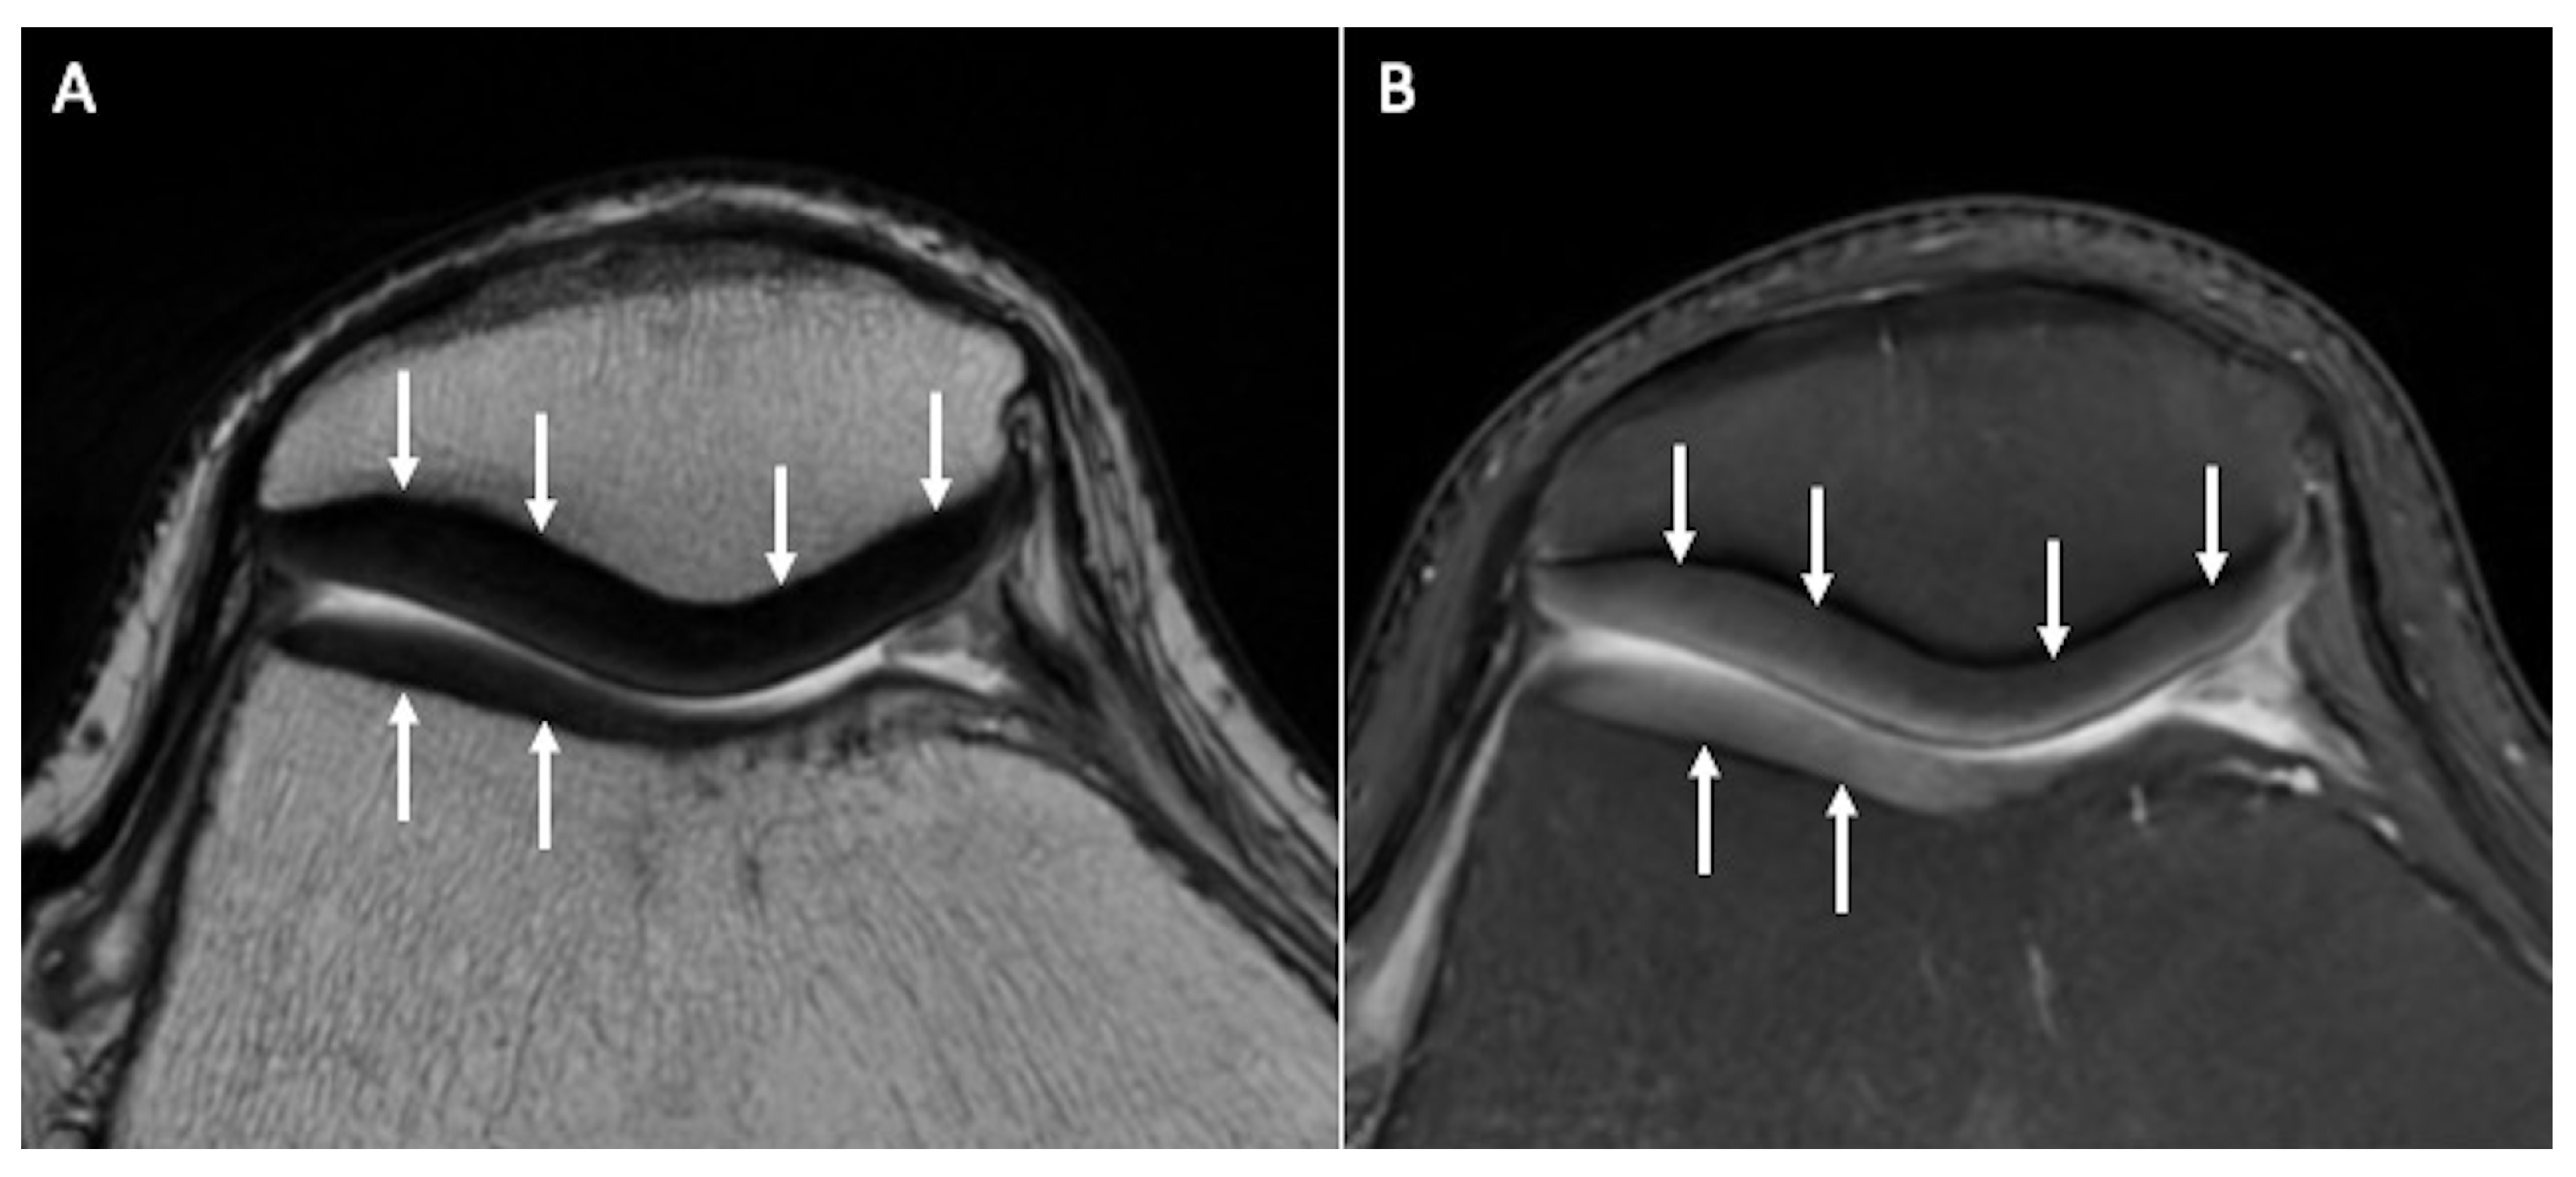

2.1. Conventional MRI

- Omoumi, P.; Mourad, C.; Ledoux, J.-B.; Hilbert, T. Morphological assessment of cartilage and osteoarthritis in clinical practice and research: Intermediate-weighted fat-suppressed sequences and beyond. Skelet. Radiol. 2023, 52, 2185–2198. [Google Scholar] [CrossRef]